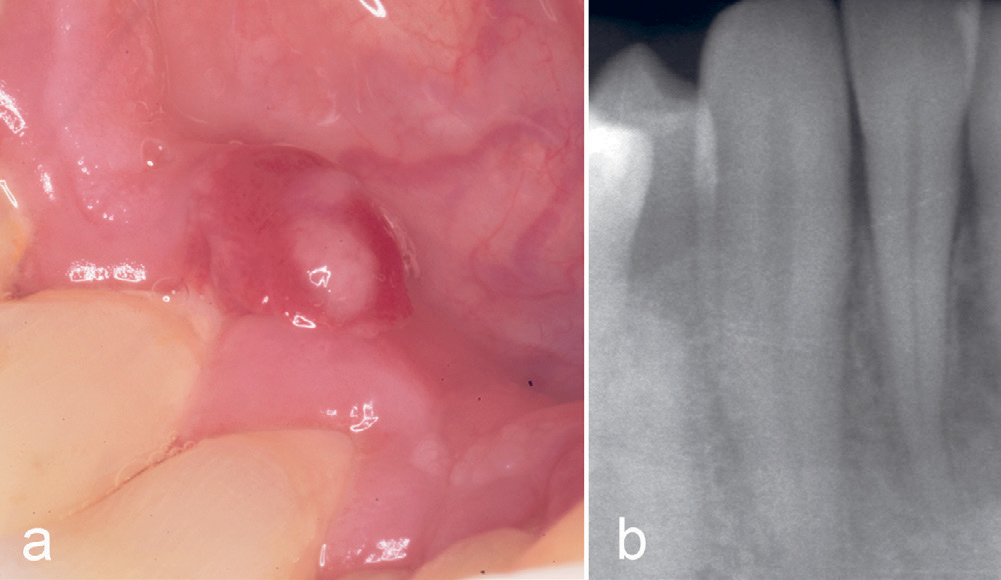

Kasus 14

En mann, 58 år, var henvist fra egen tannlege for tumor lingualt for 43. Pasienten hadde fått de første symptomene seks uker tidligere, og hadde søkt egen tannlege fire uker før henvisningen. Klinisk undersøkelse viste en rød, svakt elevert tumor med en sentral gulfarget topp (figur 11a). Et intraoralt røntgenbilde viste ingen benpatologi (figur 11b). Igjen var tentativ diagnose pyogent granulom, men nok en gang var den histologiske diagnosen PKCG.

Figur 11. Kasus 14. PKCG lingualt for tann 43 hos en 58-årig mann (a). Røntgen viste ingen patologiske forandringer (b).